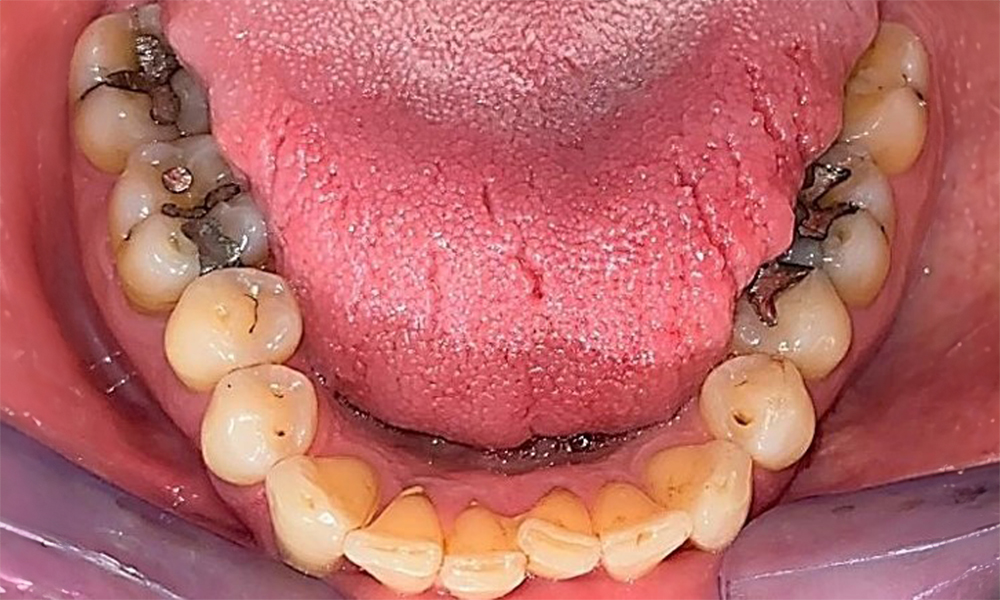

Occlusal view of the mandible showing the denture in situ.

Fig. 6 Occlusal view of the mandible showing the denture in situ. © Dr R. Krapf

The patient uses interdental brushes and an electric toothbrush. This demonstrates good compliance and good intraoral hygiene behaviour and understanding at home. Regular motivation and re-instruction are indispensable due to the risk of progression, particularly with regard to the cleaning of interdental areas, since increased probing depths were detected in these areas. Localized calculus and soft plaque was present in the lingual anterior mandibular region, and these must be shown to the patient. The interdental brush size may need to be checked and adjusted. A soft brush attachment is recommended based on the presence of exposed root surfaces to prevent wedge-shaped defects. Toothpaste with a low abrasive value should be used.